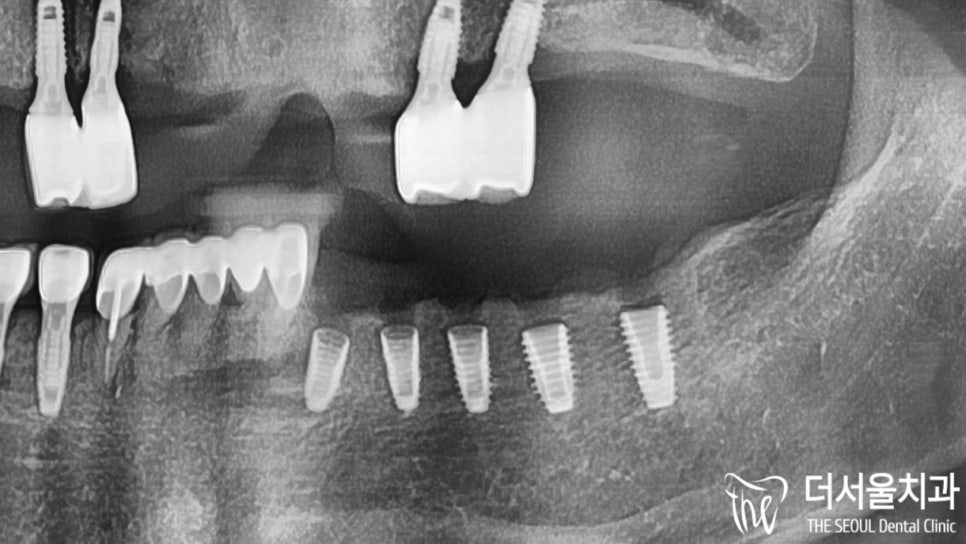

자, 모든 진단 내용을 토대로

#무절개 방식을 통해

80대 임플란트 식립을

진행하기로 계획을 세웠습니다.

치조골 소실이 나타났던 곳도

무절개로 깔끔하게 개선해 드렸습니다.

잇몸 형성 및 보철과의 연결을 도와줄

치유지대주(healing abutment)도

예쁘게 체결되어 있는 모습이네요.

총 5곳이나 심었지만

불편한 게 하나도 없었다던 환자분.

실제 치아와 유사한 형태의

지르코니아 크라운을 올려드리며

모든 과정을 마무리했습니다.